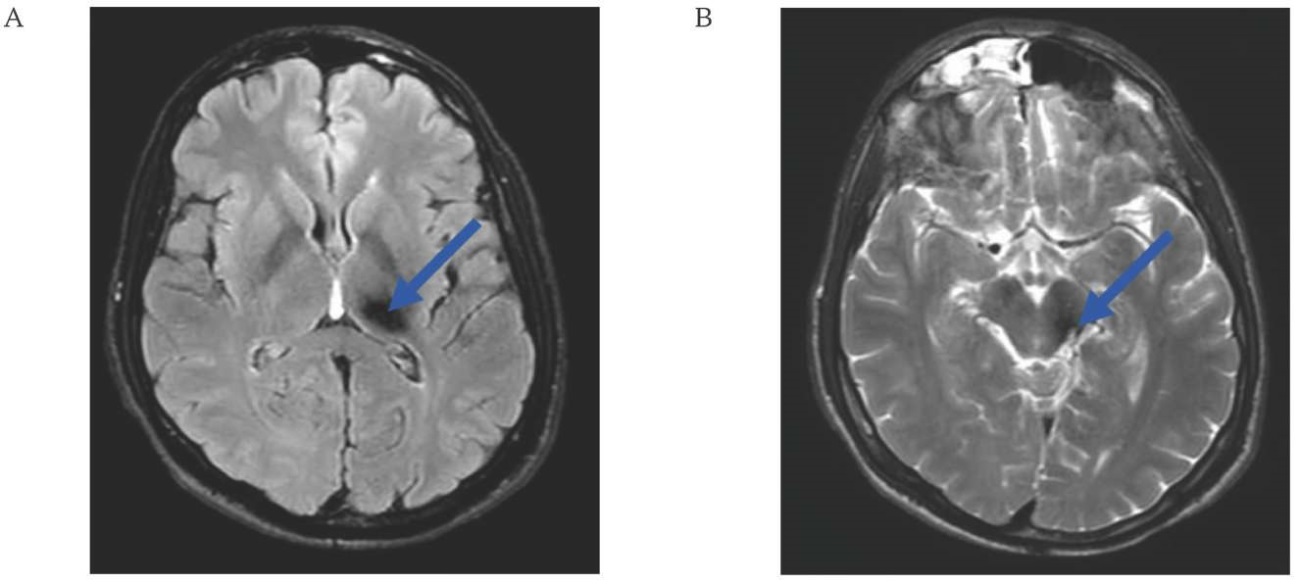

A MRI of the brain was undertaken on February 18, 2025, and here we can observe the brain’s condition after removal of the cavernoma. The MR showed signs of postoperative gliosis changes. No residual cavernoma or recurrent hemorrhage was detected (Fig. 5A, B).

FIG. 5. Magnetic resonance imaging of the brain of a 38-year-old patient 9 months after resection of a cavernous malformation in the dorsal part of the left peduncle of the midbrain (February 18, 2025)

A, B. Axial sections: postoperative gliotic changes (arrows).